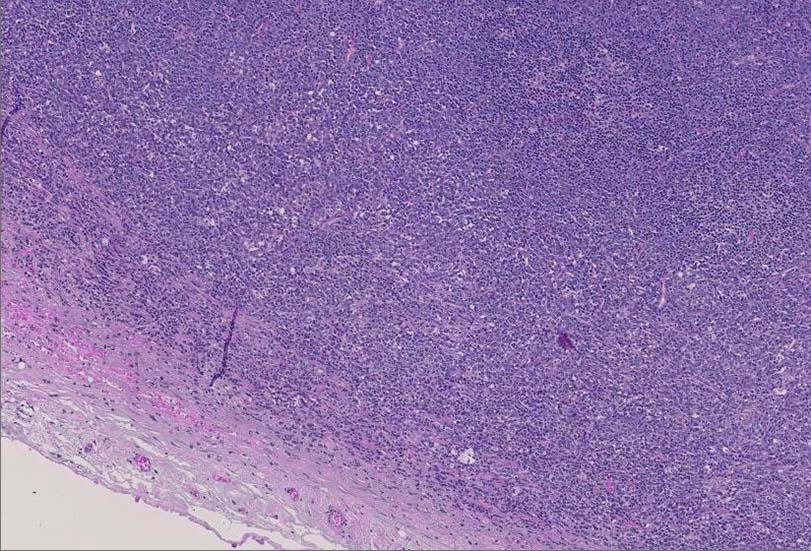

診断に難渋した顆粒球肉腫の1例 静岡赤十字病院 笠原正男: myeloid sarcomaのリンパ節病変.

腫大したリンパ節, 20x17mm. 萎縮した胚中心をもつ濾胞が散在する. 一見, Castleman病様の像. よく見ると, 線維化し軽度に肥厚した被膜下に小リンパ球の乏しい, 低倍で明るくみえる領域を視認できる.(サムネイル画像をクリックで大きな画像がみられます)